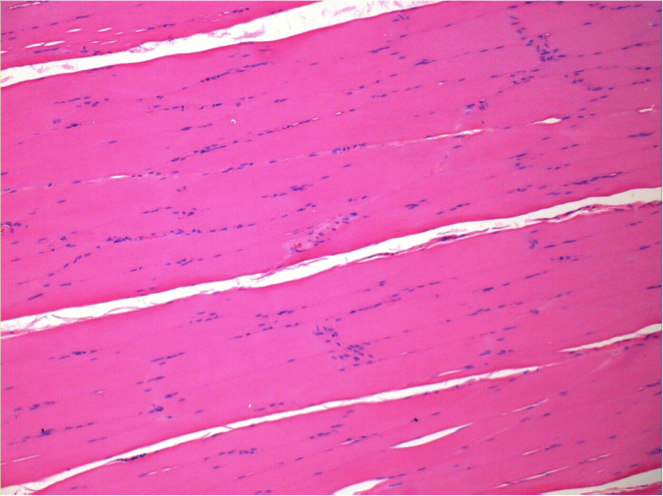

Л: Претибіальний м'яз - без лікування